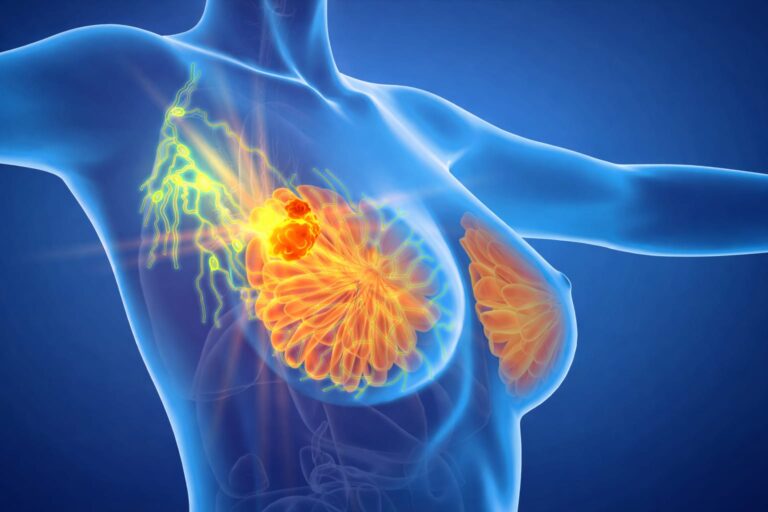

Empowering Healing: Advanced Breast Cancer Surgery in Borivali Hospital

The curtain lifts, revealing the essence of what lies ahead; curiosity meets direction in this unfolding moment Breast Conservation Surgery in Borivali.…

Essentials Breast Oncology Clinic in Mira Road. A Dr. Ramkishan Nag is a leading Breast cancer specialist in Mira Road and one…

Preface Breast Lump Removal Surgery in Mira Road. The Breast health is a vital aspect of overall wellbeing, and any abnormality such…

Essentials Advanced Breast cancer treatment in Mira Road. Breast cancer remains one of the most pressing health challenges worldwide, and surgical intervention…

Introduction Hearing the words breast cancer can feel overwhelming. If you’re here, you or someone close to you might be facing difficult decisions. One…

Healing Beyond Surviving If you’re reading this, it’s likely that you or someone close to you has been affected by breast cancer.…

Hearing a breast cancer diagnosis can change your world in an instant. It’s normal to feel a flood of emotions, fear, confusion,…

If you or someone you love is facing breast cancer, the idea of surgery can feel overwhelming. In this guide, we’ll walk…

Breast Conservation Surgery In Mira Road If you’re reading this because either you or someone you love has recently been diagnosed with…